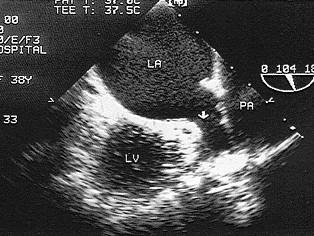

该图箭头显示图像为?(?)A.左心耳B.肺静脉C.右心耳D.上腔静脉E.下腔静脉

问题 该图箭头显示图像为?(?)

选项 A.左心耳 B.肺静脉 C.右心耳 D.上腔静脉 E.下腔静脉

答案 A